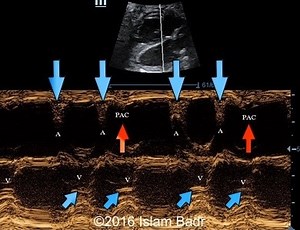

Heart Rhythm - Pac EKG

Trigeminy - Ectopic Heart

Heart Rhythms - Trigeminy Rhythm